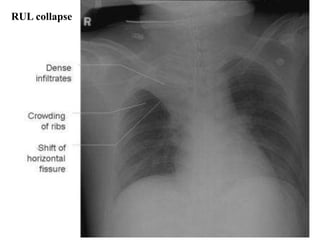

RUL collapse

Atelectasis/collapse

• Severe atelectasis

– Opacification of all or a whole lobe or several

segments of a lobe, associated with volume

loss:

– + crowding of vessels

– + crowding of ribs

– + shift of structures such as interlobar fissures

or the hilum towards areas of lung volume loss

– + elevation of the hemidiaphragm

– Compensatory hyperinflation

Major differentiating factors

between atelectasis and pneumonia:

Atelectasis/collapse Consolidation

Loss of lung volume Normal lung volume

Anatomy shifts

towards atelectasis

No anatomical shift

Linear, smooth,

wedge-shaped

Consolidation

Apex of opacity starts

at hilum

Air bronchograms can occur in both.